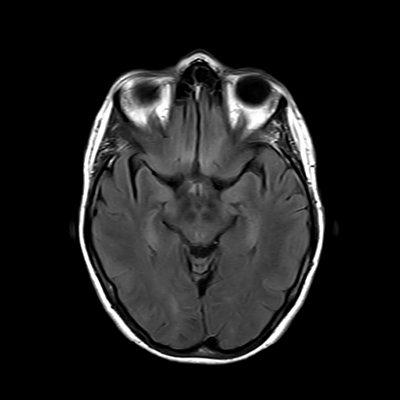

You also obtain an MRI of his brain once it's clinically safe to do so.

MRI brain (FLAIR)